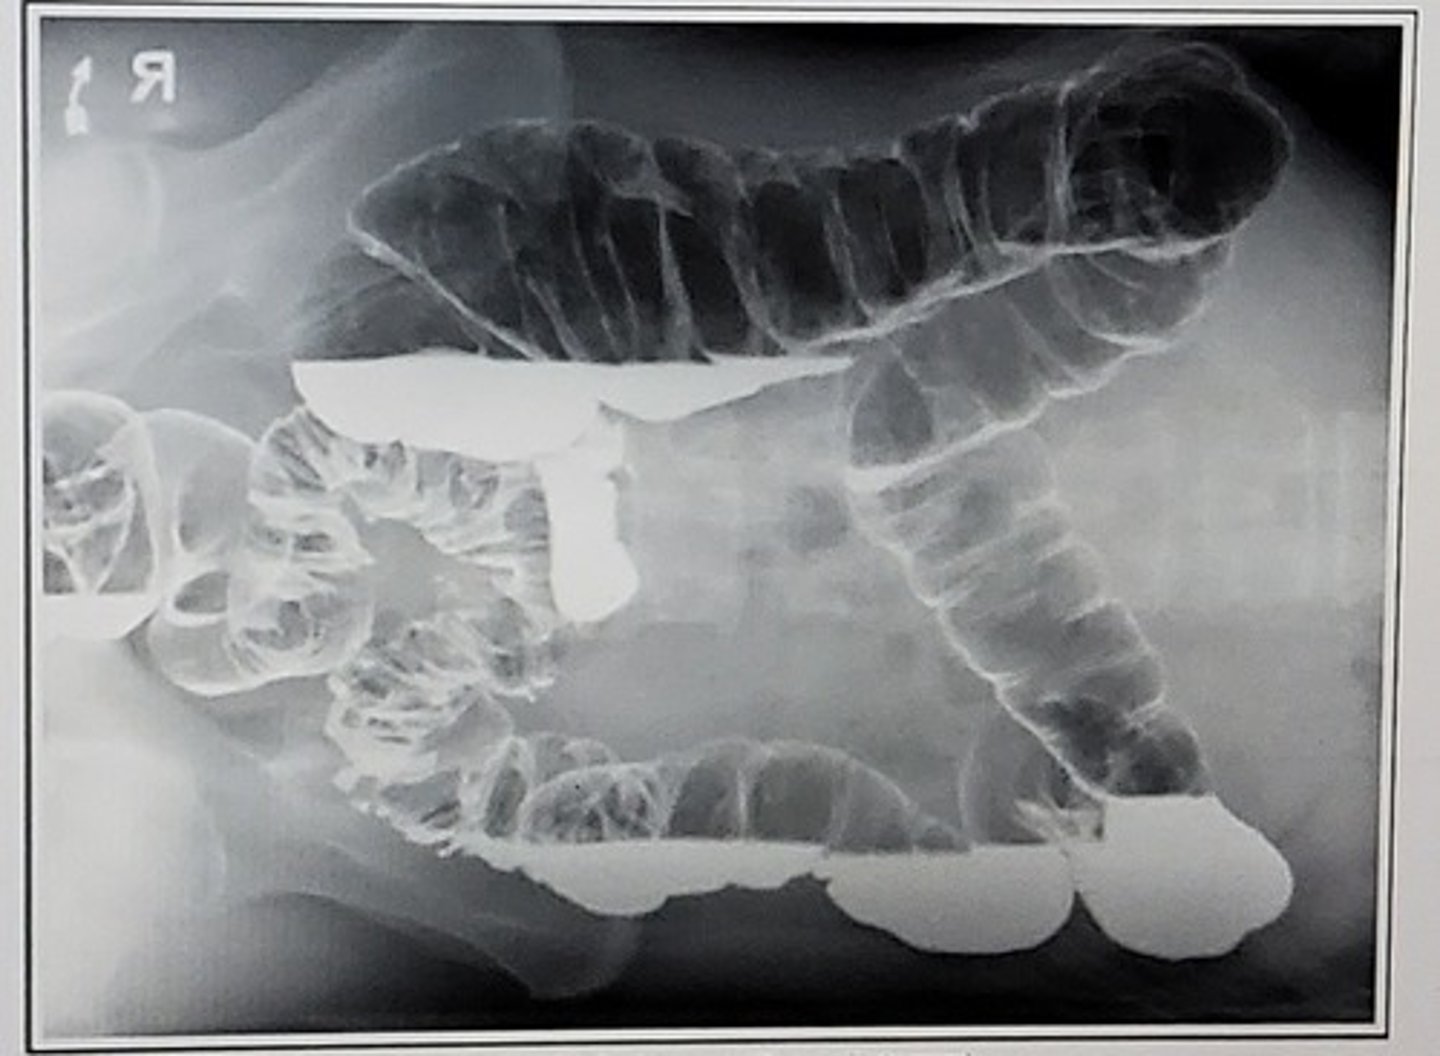

B. PA, RAO

Select the projection used to create this image:

A. AP, RPO

C. AP, supine

D. Right lateral